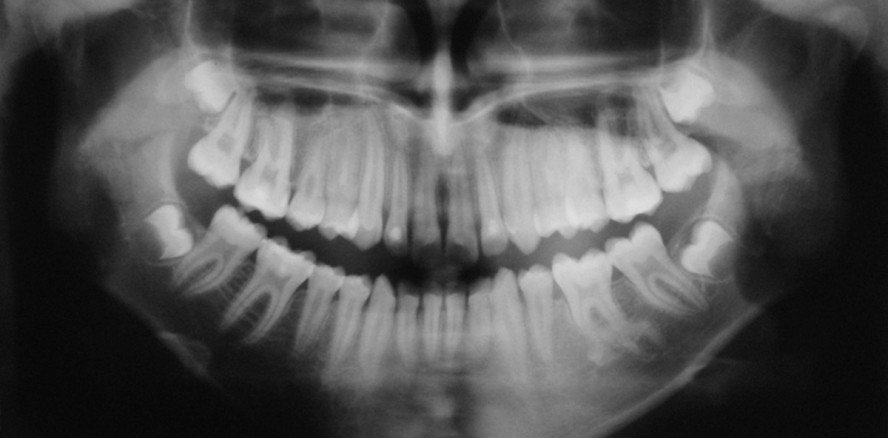

Ein 17-jähriger Patient stellte sich in Begleitung seiner Eltern mit einer Überweisung zur Weisheitszahnentfernung in der Fachpraxis für Oralchirurgie vor. Die angefertigte Panoramaschichtaufnahme zeigte als Zufallsbefund eine dichte Verschattung im periardikulären Bereich des Zahns 36 (Abb. 1).1, 2 Der Patient gab keine Beschwerden an und war klinisch symptomlos. Die Sensibilitätsprobe war ohne Auffälligkeiten und die Anamnese ergab keinen Hinweis auf ein Trauma. Zur weiterführenden Diagnostik und zum Ausschluss einer malignen Knochenveränderung erfolgte eine dreidimensionale Bildgebung.1, 3–7 Zum Erstellen der Diagnose und um die Strahlenbelastung niedrig zu halten, wurde zuerst eine kleinvolumige digitale Volumentomografie (DVT) angefertigt (FOV 50 x 37 mm).3–8

Wie die Abbildungen 2 und 3 zeigen, bildet die im Panoramaröntgenbild dargestellte Verschattung (wolkige mineralisierte Strukturverdichtung im periapikalen Bereich) einen überzähligen rudimentär retinierten Zahn in Situs inversus ab.4, 6, 7 Es zeigte sich eine s-förmige Wurzeldilazeration an beiden Wurzeln mit einer Angulation des mittleren Drittels nach distal und des basalen Drittels nach kaudal. Ein Trauma, retinierter überzähliger Zahn oder Odontom kann die Form eines Zahns während des Wachstums beeinträchtigen. Diese Änderung beider Wurzeln im vorliegenden Beispiel geht vermutlich auf diesen retinierten überzähligen Zahn und das spezielle Wachstum des Unterkiefers in dem Alter des jungen Patienten zurück (Abb. 3).5, 7, 9–11 Wenn wir die S-Form dieser zwei Wurzeln sehen, wird einmal mehr deutlich, dass keine Computergrafiksoftware ein besseres Bild hätte liefern können.